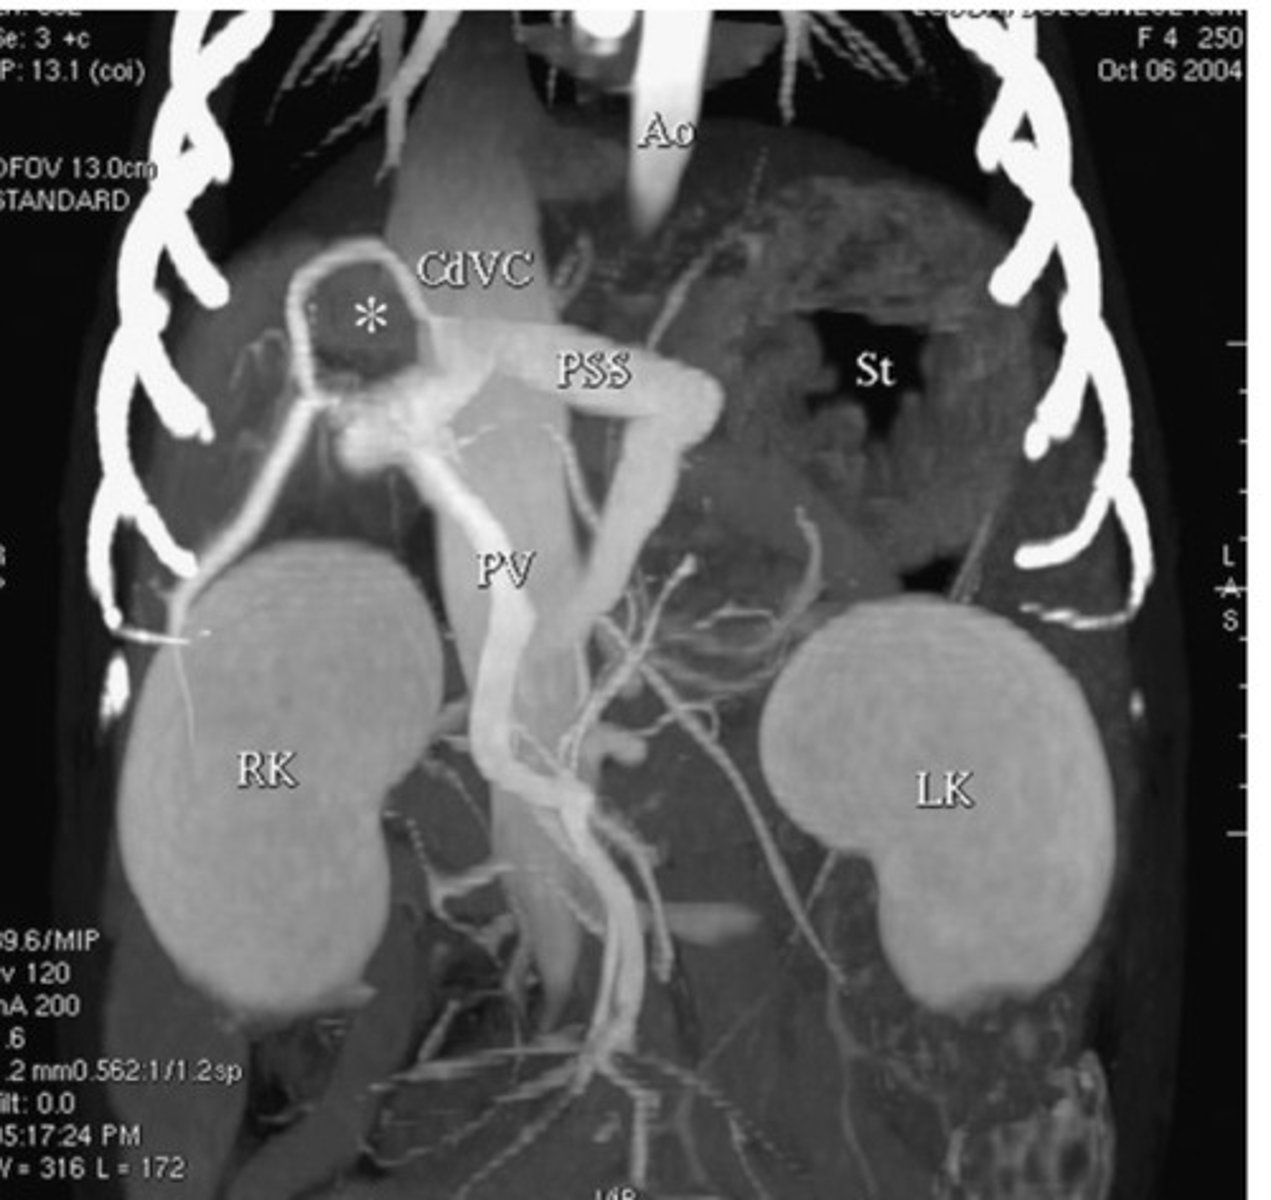

What hepatic abnormality is computed tomography best at imaging?

CT

What form of imaging is this?